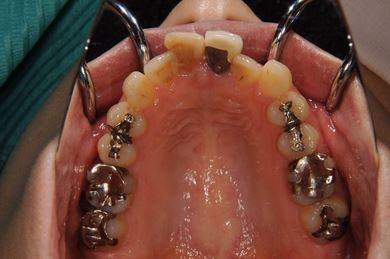

全顎矯正治療+セラミック治療

| 治療方針 | 上下歯牙がだいぶ前にでていて口が閉じづらい状態でした。なるべく金属が入っている歯を抜歯したいので、上下左右第二小臼歯を抜歯して、その隙間を利用して、口元をさげていきました。また、口元を最善の状態にうるために、抜歯スペースを使用したあと、上下左右のインプラントアンカー(釘)でより一層口元を後ろにさげていきました。ただの抜歯ケースよりだいぶ口元が下がっているのが分かります。抜歯したスペースががたつき(叢生量)で使用してしまう場合には、このような方法でより口元をさげることができます。お顔立ちがとてもよくなりました。とても協力していただけたので、しっかりと良くなることができました。 | ||||||||||||||||||||||||||||||||

| 治療内容 | 唇側矯正(ホワイト・上下左右第二小臼歯抜歯・上下インプラントアンカー)、オールセラミッククラウン1本(オールセラミック用土台1本)、ジルコニアフレームオールセラミッククラウン1本 | ||||||||||||||||||||||||||||||||